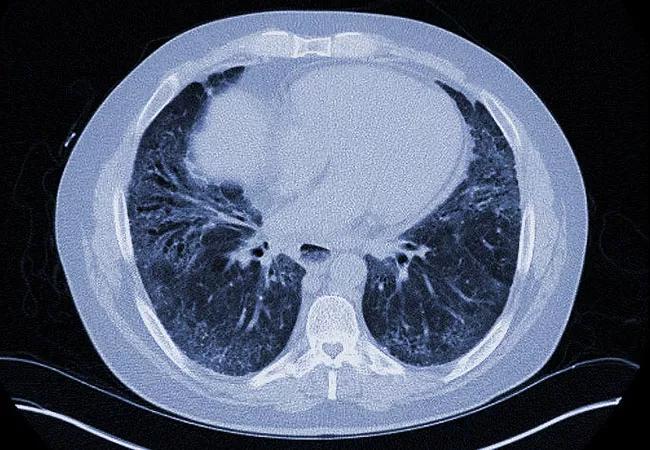

Results from a just-published landmark trial could lead to the first-ever approved drug for the treatment of systemic scleroderma-associated interstitial lung disease.

Systemic sclerosis (SSc) is a relatively rare, heterogeneous autoimmune disease characterized by immune dysregulation, microvascular damage and organ fibrosis. About 40% of SSc patients experience interstitial lung disease (ILD), a major cause of morbidity and mortality.

A total of 576 patients with SSc were treated in the study, including 51.9% with diffuse cutaneous SSc and 48.4% who were taking mycophenolate at baseline. All had onset of their first non-Raynaud symptom within the past seven years and at least 10% fibrosis of the lungs on high-resolution computed tomography scan.